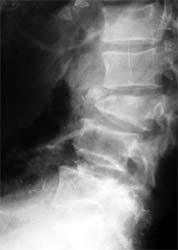

患者男性,30岁,腰3骨折,截瘫

CT显示腰3椎体爆裂,骨块凸入椎管压迫硬膜囊

施行后路椎管前方减压术及经椎弓根固定植骨术,彻底解除 脊髓前方的压迫及后凸畸形,截瘫部分恢复